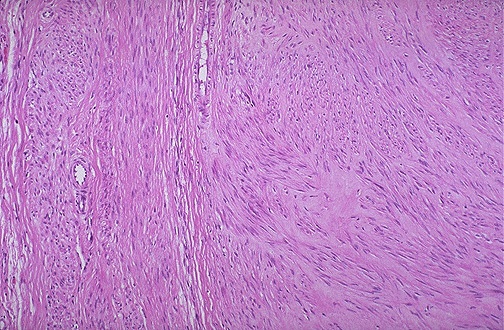

| Here is the microscopic appearance of a benign leiomyoma. Normal myometrium is at the left, and the neoplasm is well-differentiated so that the leiomyoma at the right hardly appears different. Bundles of smooth muscle are interlacing in the tumor mass. |